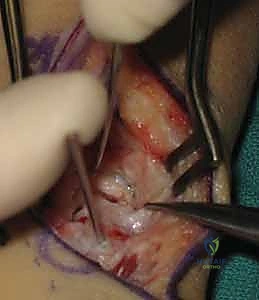

2. تنظيف موقع عدم الالتئام (Debridement)

بمجرد الوصول إلى العظم الزورقي، يقوم الجراح بإزالة النسيج الليفي المتكون بين شظايا العظم. ثم يتم استخدام أدوات دقيقة (Curettes or high-speed burrs) لكشط وحفر حواف العظم المتصلبة والميتة حتى يتم الوصول إلى عظم إسفنجي صحي ينزف دماً. هذه العلامة تُعرف طبياً بـ "علامة البابريكا" (Paprika Sign)، وهي مؤشر حاسم على أن العظم المتبقي حي وقادر على الالتئام.

3. أخذ الرقعة العظمية الذاتية (Harvesting the Bone Graft)

لتحفيز الالتئام وسد الفجوة الناتجة عن تنظيف الكسر، يحتاج الجراح إلى عظم جديد. يقوم الأستاذ الدكتور محمد هطيف عادة بأخذ قطعة صغيرة من العظم الإسفنجي من نهاية عظمة الكعبرة (Distal Radius) في نفس اليد، أو من عظمة الحوض (Iliac Crest) إذا كانت الفجوة كبيرة. يتم تشكيل هذه الرقعة العظمية بمهارة فائقة لتأخذ شكل "وتد" (Wedge).